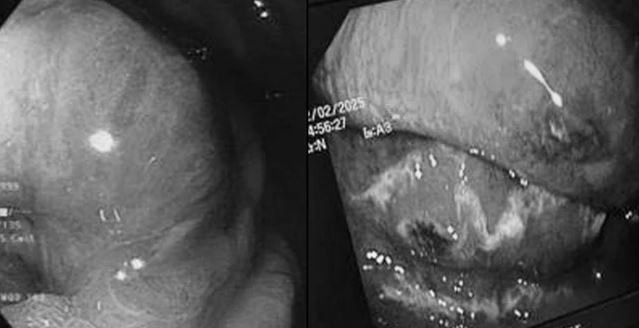

Kết quả chụp cắt lớp vi tính ổ bụng và nội soi dạ dày thực quản cho thấy phần lớn thành thực quản và dạ dày của người bệnh bị viêm, phù nề kèm theo hoại tử sinh hơi; niêm mạc thực quản - dạ dày xung huyết và mủn nát.

Bệnh cảnh của người bệnh phù hợp với chẩn đoán viêm hoại tử sinh hơi dạ dày thực quản (tên tiếng Anh: Emphysematous Esophagogastritis). Đây là thể bệnh hiếm gặp, trên y văn thế giới mô tả chủ yếu thể viêm hoại tử dạ dày đơn độc, chỉ có khoảng 10 báo cáo ca bệnh bao gồm tổn thương diện rộng cả thực quản và dạ dày, trong đó chưa có trường hợp nào ghi nhận do vi khuẩn Streptococcus constellatus.